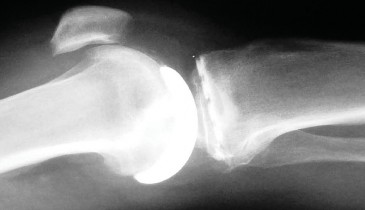

التصوير الطبي ضروري لتأكيد التشخيص وتحديد مدى تلف المفصل:

-

الأشعة السينية العادية (Plain Radiographs):

- المنظر الأمامي الخلفي (AP): يُظهر الركبة من الأمام.

- المنظر الجانبي (Lateral): يُظهر الركبة من الجانب.

- المنظر الخلفي الأمامي المثني (PA Flexed): يسمح بتقييم أفضل للجزء الخلفي من الركبة وقد يكشف عن تغيرات أكبر في الحجرة الخلفية الوحشية.

- منظر شروق الشمس (Sunrise/Patellofemoral): لتقييم المفصل الرضفي الفخذي.

- الأشعة السينية الطويلة للطرف السفلي بالكامل (Full-length standing radiographs): من الورك إلى الكاحل، وهي مفيدة جدًا، خاصة إذا تم استخدام تقنيات الملاحة الحاسوبية. تُظهر هذه الأشعة المحاذاة الكلية للطرف السفلي.